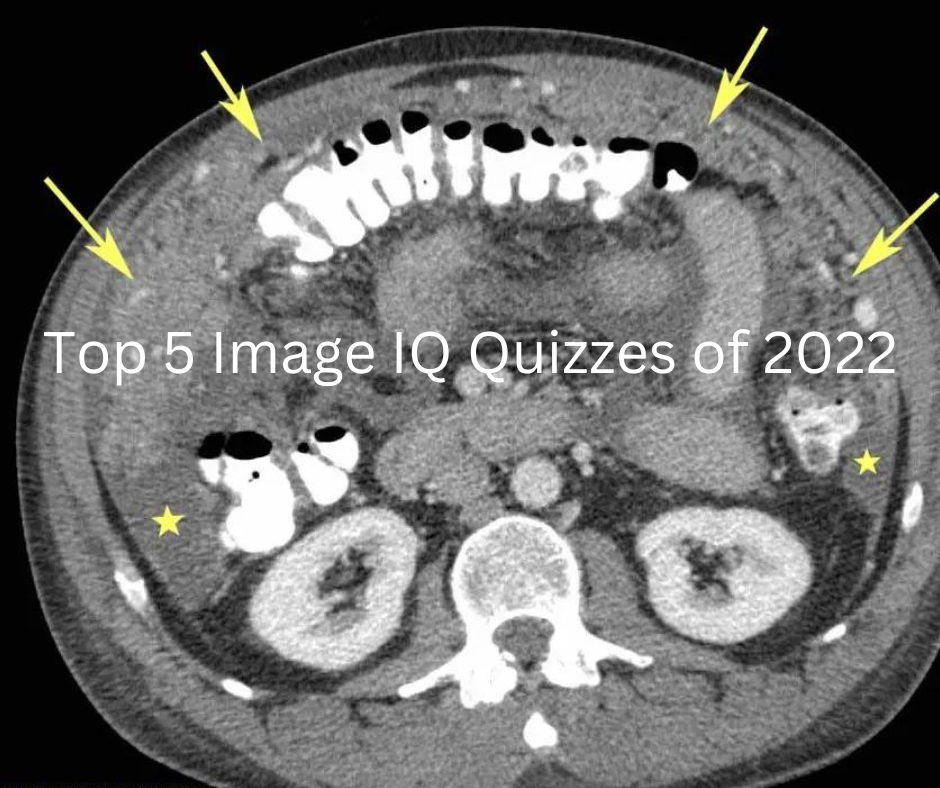

From www.diagnosticimaging.com

Diagnostic Imaging's Top 5 Image IQ Quizzes of 2022 Diagnostic Radiology Lab Quiz Case quizzes help improve healthcare education by letting medical professionals world wide undertake self. Study with quizlet and memorize flashcards containing terms like killivolts peak (kvp), milliamperes (ma), milliamperes/seconds. Which of the following individuals is at particular risk for osteoporosis? Study with quizlet and memorize flashcards containing terms like indications for diagnostic radiology, advantages of radiology,. Study with quizlet and. Diagnostic Radiology Lab Quiz.